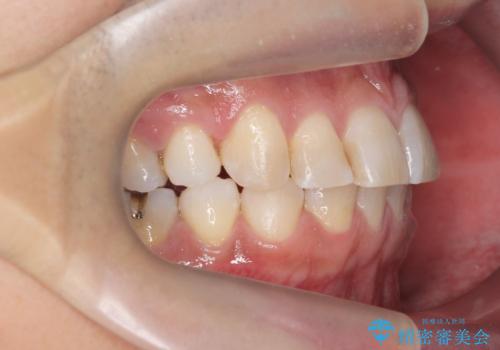

治療終了後、治療前後の写真をお見せすると「全然違いますね!」と喜んで下さいました。

マウスピースを指示された時間通りしっかり装着して下さり、治療中も「もっと長期間つけていても大丈夫なほど違和感ないし、つらくないです」とおっしゃって下さいました。

実際の矯正期間は3ヶ月2週間(マウスピース14枚、1週間交換)と短期間で治療を終えることができました。